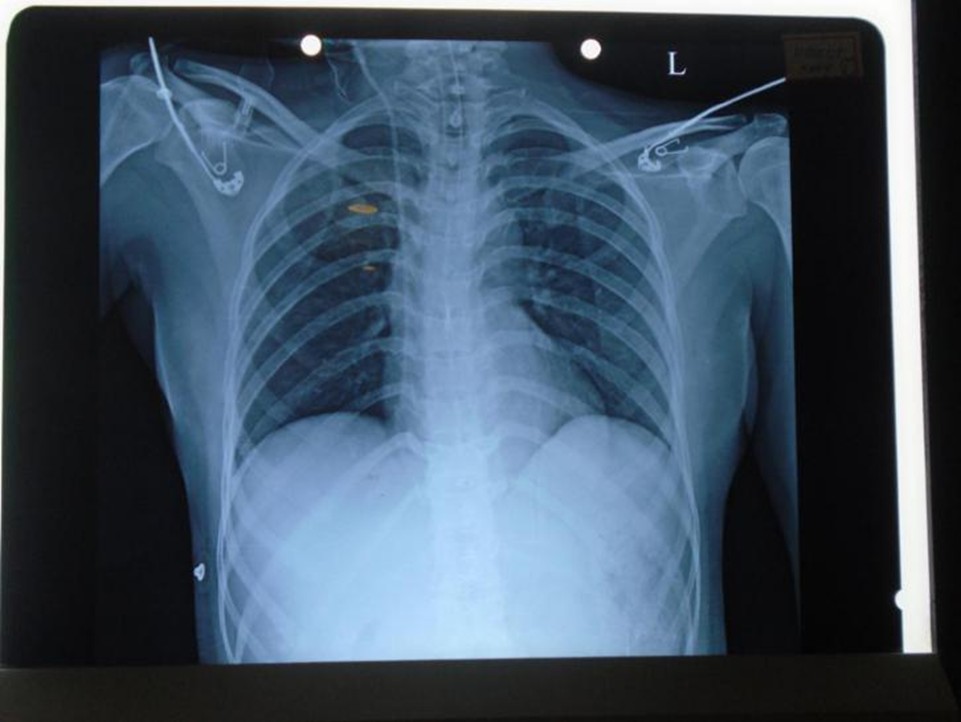

Pre OP X-Ray